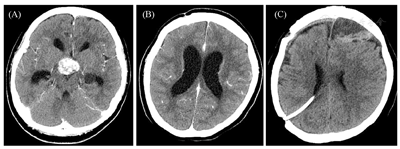

患者女性,22岁,因"头痛伴停经1年余,发现血糖升高7个月"之主诉于2018年1月入住本科。1年前因"头痛伴停经"诊断为"颅咽管瘤",10个月前在国外医院检查,晨8∶00血皮质醇14.0 μg/dl(参考范围5.0~28.0 μg/dl,下同)、促甲状腺激素(TSH)2.62 μIU/ml(0.5~4.5 μIU/ml)、FT4 0.9 ng/dl(0.8~1.8 ng/dl),行头颅磁共振(MRI)三维重建检查,诊断为"颅咽管瘤",行"经鼻蝶窦肿瘤切除术"联合"头颅穿孔减压术+去除肿瘤囊性部分"治疗,手术病理示:"乳头型颅咽管瘤(BRAF V600E突变阳性)",术后出现腺垂体功能减退、视野缺损及尿崩症等一系列相关并发症,分别给予"氢化可的松、左甲状腺素钠、去氨加压素"等药物治疗,临床症状好转(图1)。8个月前再次因"头痛"在另一国外医院诊断为"脑积水",给予"脑室腹腔分流置管术"治疗(图2)。7个月前出现精神差、偶有幻觉、短时记忆受损,复查发现"颅内肿瘤增大",于国外当地医院行放射治疗30次(放疗累积总剂量为54 Gy),为防治"脑水肿"给予口服"地塞米松4~8 mg/d"2月余,逐渐出现食欲增大、血糖增高,多次监测空腹血糖>8 mmol/L(3.9~6.1 mmol/L),伴体重增加、嗜睡、少动,未予药物治疗。4个月前再次复查"颅内肿瘤体积增大",于国外医院行"开颅肿瘤切除术"(图3),术后停用"地塞米松",改为"泼尼松40 mg/d"治疗,逐渐减量;治疗过程中逐渐出现肥胖,体重共增加约50 kg,腹部及四肢皮肤出现宽大紫纹,监测血糖升高,空腹血糖最高达15~16 mmol/L,自服"二甲双胍1.0 g/d",未规范治疗。

注:(A)、(B)术后脑积水改变;(C)脑室腹腔分流置管术后